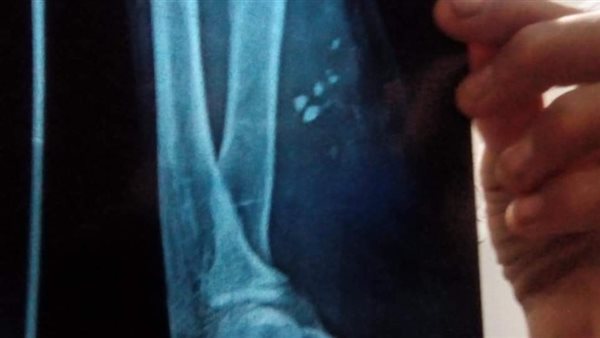

اتجه إلى محافظة القاهرة؛ لإجراء بعض الفحوصات الطبية؛ نظرًا لأنه يشعر بألم شديد وتم عمل أشعة ليتبين أن الجرح بداخله زجاج ولا بد من عمل جراحة عاجلة لتنظيف الجرح وإعادته مرة أخرى.

أشار حسن عبده الصعيدي إلى أن الزجاج ظل داخل ذراعه ما يقرب من 40 يومًا حتى إخراجه بعد عمل جراحة في أحد المستشفيات بمحافظة القاهرة، مطالبًا المسؤولين بمحافظة شمال سيناء بمحاسبة الدكتور المعالج بمستشفى العريش الذي لم يراعِ الله في عمله، وأغلق الجرح دون تنظيفه؛ ما تسبب في ألم جسدي على مدار 40 يومًا.